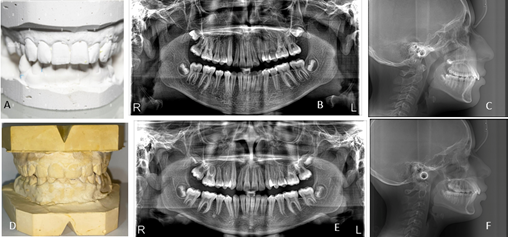

Al análisis radiográfico se muestra, en la radiografía panorámica del caso 1 la presencia de piezas dentales erupcionadas 17,16,15,14,13,12,11, 21,22,23,24,25,26,27, 37,36,35,34,33,32,31,41,42,43,44,45,46,47; órgano dental n° 18,28,38,48 en proceso de formación; proporción corona-raíz de los órganos dentarios adecuada, niveles de la cresta ósea con altura adecuada; sin signos de enfermedad periodontal; cóndilos aparentemente simétricos y presencia de cornetes normales.

En el caso 2, se observa la presencia de piezas dentales erupcionadas 16,15,14,13,12,11,21,22,23,24,25,26,36,35,34,33,32,31,41,42,43,44,45,46; órgano dental 17 y el 47 en proceso de erupción; órgano dental 27 y 37 parcialmente erupcionados; proporción corona-raíz de los órganos dentarios adecuada; niveles de la cresta ósea con altura adecuada; sin signos de enfermedad periodontal; cóndilos aparentemente simétricos y presencia de cornetes normales.

La radiografía cefálica lateral muestra para el caso 1, un valor de sobremordida horizontal (B1-A1) de +5 mm que refleja una sobremordida; en la sobremordida vertical (B1-A1) el paciente presenta +4.6 mm lo que indica una mordida profunda; la convexidad (A/N - pog) es de +7 mm que revela Clase II esquelética; la protrusión del incisivo superior (A1/A-poq) muestra un valor de +7mm que indica la presencia de Incisivo superior protruido. En el caso 2 muestra un valor de sobremordida horizontal (B1-A1) de +5 mm que refleja sobremordida; en la sobremordida vertical (B1-A1) el paciente presenta +5mm lo que indica mordida profunda; la convexidad (A/N - pog) es de +6mm que revela Clase II esquelética; valor de protrusión labial (Li/Pn-Dt) +2mm que indica un labio inferior protruido.

Figura 2. Radiografía panorámica y Modelo en vista oclusal frontal

Elaboración: Los autores.